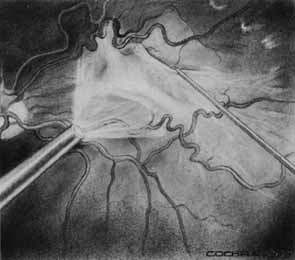

Optical coherence tomography or OCT is a relatively new tool used to diagnose macular lesions. It provides a unique view of the vitreoretinal architecture. OCT is particularly useful in diagnosing lamellar holes. With improvements in resolution and more widespread use, OCT will lead to new advances in the diagnosis and pathogenesis of macular holes (Fig. 2).